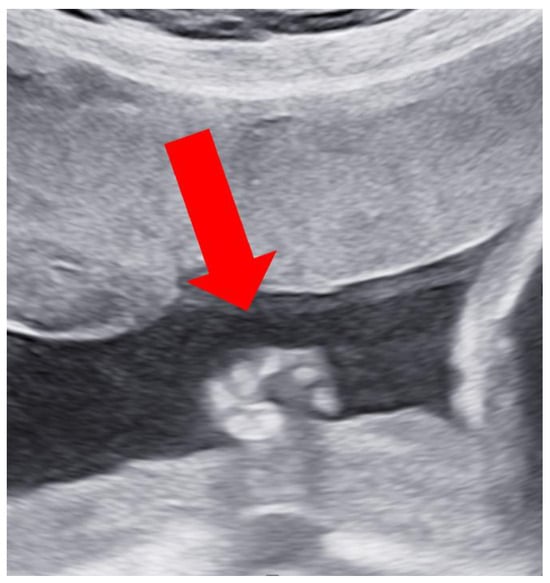

Case Report